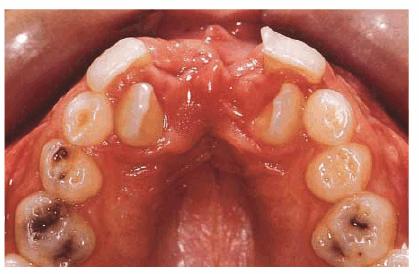

A male patient, 8 years, 3 months old.

PROBLEM: The patient presented with a supernumerary incisor and a double

tooth in place of the central upper left incisor (tooth #9) (Figures 27-11A and B). This anomaly manifests itself as a

structure resembling two teeth that have been joined together. In the anterior

region, the anomalous tooth usually has a groove on the buccal surface and a

notch in the incisal edge. Radiographs are necessary to determine if there is a

(fusion) union of the pulp chambers. Fusion exists when there is a joining of

two teeth by pulp and dentin. Two canals are usually present, as in this case.

Figure 27-11A and B: A supernumerary incisor and a double tooth in place of the central upper left incisor. Frontal and occlusal views.

TREATMENT: Both the supernumerary tooth and fused tooth were extracted (Figure 27-11C); also, the fixed orthodontic appliance was

applied to the maxillary arch to close the anterior diastema. Subsequently, the

incisal margin and the interproximal area of tooth #9 were restored to improve

esthetics (Figure 27-11D).

Figure 27-11C: Both the supernumerary tooth and fused tooth are extracted.

Figure 27-11D: An orthodontic appliance is applied to the maxillary arch to close the anterior diastema.

RESULT: The team work of several specialists created a good

morphic-functional recovery (Figures 27-11E and F) and an esthetic result that satisfied

the patient (Figures 27-11G and H).

Figure 27-11E and F: The morphic-functional recovery at the end of the orthodontic treatment.

Figure 27-11G and H: The final result showing the patient's smile at the end of the treatment.